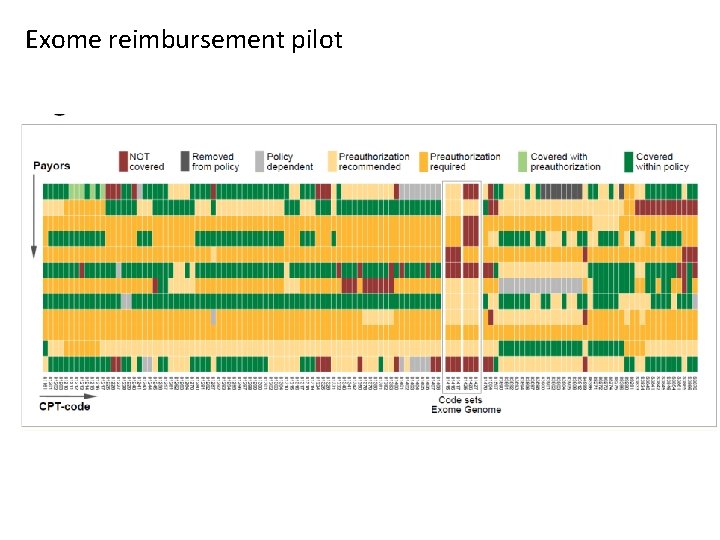

Exome reimbursement pilot